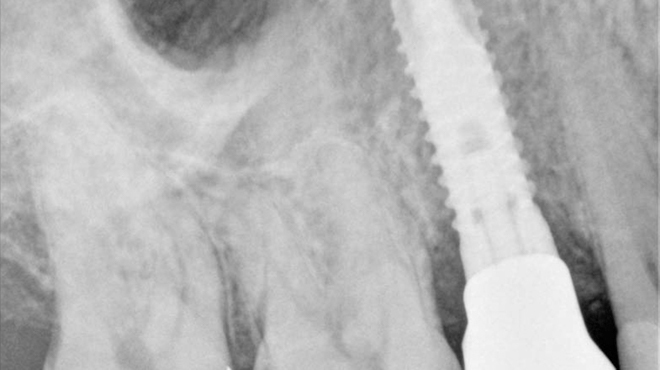

Atraumatická extrakce horního levého moláru kleštěmi Physics Forceps

Assist. Prof. Suphachai Suphangul | Parinya Amornsettachai, DDS, MSc, Bangkok, Thajsko

Extrakce mohou být stresující procedurou jak pro pacienta, tak pro zubního lékaře...